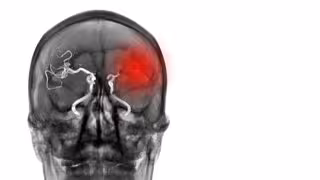

Archivo - Aneurisma

Archivo - Aneurisma - SITTITHAT TANGWITTHAYAPHUM/ISTOCK - Archivo

Un aneurisma es un abultamiento o debilitamiento de la pared de una arteria. Cuando esto ocurre en una arteria del cerebro, se denomina aneurisma intracraneal. Si un aneurisma intracraneal se rompe, derrama sangre por el cerebro y corta el oxígeno de la zona afectada, lo que puede causar un ictus hemorrágico, coma y muerte.